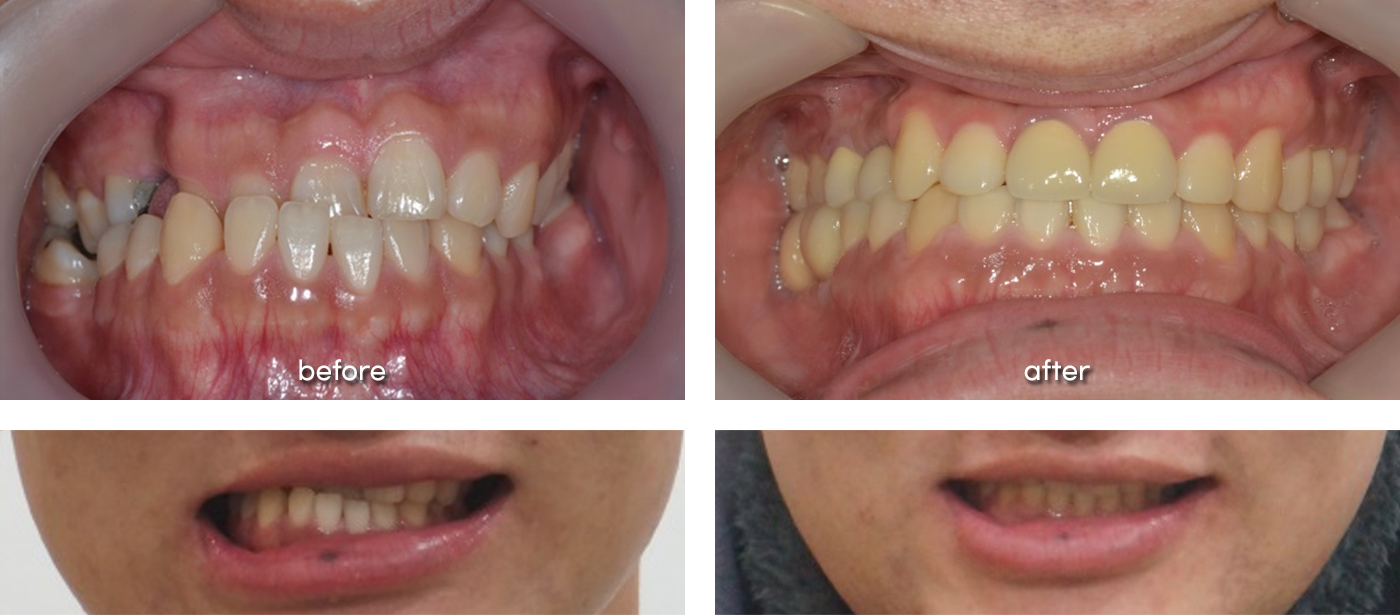

- 초진

- 앞니가 반대로 물리고 비대칭도 심해서 타치과에서 수술교정 권유받고 내원

- 치료 후

- 비수술 교정치료만으로도 입술 비대칭이 개선